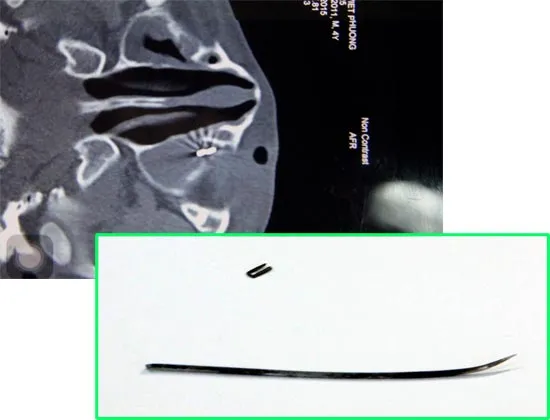

Sau khi chụp citi, các bác sĩ thấy một mạch máu lớn của bệnh nhân bị thủng, nếu không phẫu thuật kịp thời bệnh nhân sẽ sốc mất máu tử vong hoặc có thể máu sẽ chảy tràn vào xoang màng phổi gây suy hô hấp.

Hiện tại bệnh nhân đã qua nguy kịch, có thể nói chuyện, ăn uống được tuy vậy đầu đạn vẫn còn nằm trong cơ thể, gần đốt sống và chưa thể lấy ra.

Theo bác sĩ Duy Tân, hiện tại đầu đạn đã nằm cố định, không ảnh hưởng đến tính mạng nên sau khi bệnh nhân bình phục sau cuộc phẫu thuật thì sẽ tiếp tục phẫu thuật để lấy đầu đạn ra.